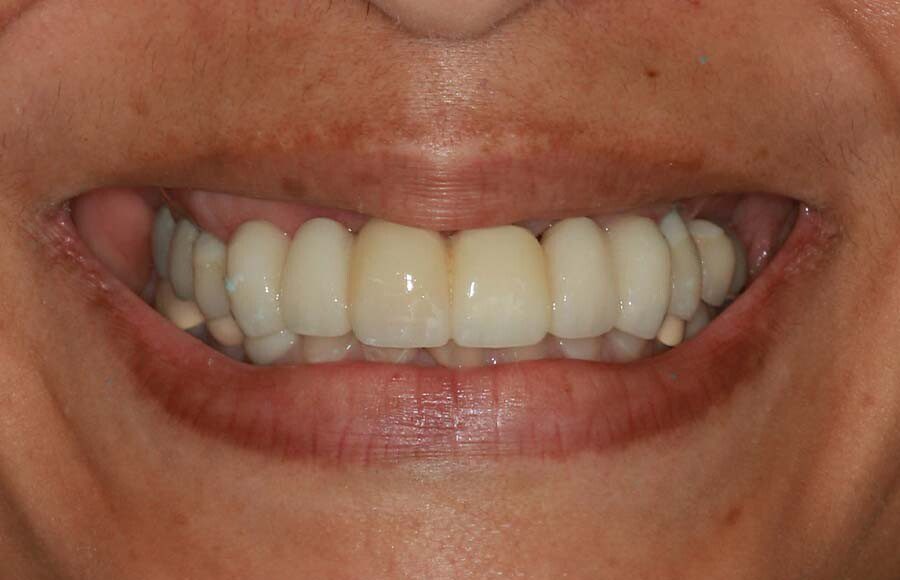

Smile GalleryImplant RestorationsFull Mouth Implant Restoration Full arch zirconia implant bridge (full smile) 1 of 37 Pre-op full smile Pre-op lips retracted Pre-op panoramic x-ray Extraction of strategic teeth Placement of implants Extraction of some remaining teeth after verification of adequate implant stability Occlusal view Post-op panoramic x-ray Immediately fabricated provisional restoration (tissue side view) Immediately fabricated provisional restoration (occlusal side view) Immediate provisional delivered on day of surgery Immediate provisional 2 weeks later Scalloped tissue developed from the provisional at 2 weeks Jig used for making a master impression Provisional in place (full smile) Provisional in place (lips retracted) Provisional in place (right side) Provisional in place (left side) Wax try-in (full smile) Wax try-in (right side full smile) Wax try-in (left side full smile) Wax try-in (full face, lips together) Wax try-in (full smile) Wax try-in (right side) Wax try-in (left side) Wax try-in (lips retracted) Full arch zirconia implant bridge on master cast (frontal view) Full arch zirconia implant bridge on master cast (occlusal view) Implant positions and soft tissue representation on master cast (occlusal view) Soft tissue representation on master cast (frontal view) Full arch zirconia implant bridge (tissue side view) Soft tissues on day of delivery (occlusal view) Soft tissues on day of delivery (frontal view) Full arch zirconia implant bridge delivered (lips retracted) Full arch zirconia implant bridge (lips retracted, close up) Post treatment panoramic x-ray Full arch zirconia implant bridge (full smile)